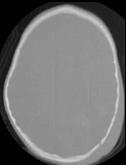

- 单项选择题男,3岁, 头颅被球击中,请结合CT图像, 选择最可能的诊断是 ( )

A、高血压性脑出血

B、脑结核

C、脑挫裂伤血肿形成

D、动脉瘤破裂出血

E、血管畸形